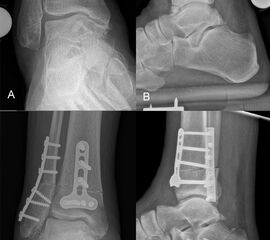

Native Röntgenaufnahmen des Sprunggelenks in 2 Ebenen unter Belastung (antero-posterior und lateral) erlauben Gelenkspaltverschmälerung, osteophytäre Anbauten sowie Achsfehlstellungen zu beurteilen. Eine „Canale-Aufnahme“ (Pronation des Fußes von ca. 15 °, Röntgenstrahl 75 ° nach kranial) 9 kann hilfreich sein, die subchondralen Oberflächen einzusehen. Die korrekte Abbildung der Sprunggelenkgabel in der sogenannten „Gabel-Aufnahme“ (mortise-view) ist zudem notwendig zur Beurteilung der Gelenkkongruenz. An Grenzen stößt die konventionelle Röntgenaufnahme allerdings bei OCLs ohne weitere knöcherne Veränderungen. Bis zu 50% der OCLs sind auf konventionellen Röntgenaufnahmen nicht sichtbar. Auch kann der Zustand des Knorpels nicht beurteilt werden 10. Bei Achsfehlstellungen werden zusätzlich Rückfußachs-Aufnahmen (Saltzman View) angefertigt bzw. eine Einbeinstandaufnahme zur Bestimmung der Becken-Bein-Achse.

Zur Vollansicht und zum Lesen der Bildbeschreibung bitte das Bild anklicken.

Der Computertomographie (CT) fehlt ebenfalls die Fähigkeit, den Knorpel direkt zu bewerten. Mit dem CT können jedoch weitere Details der knöchernen Verletzung, wie Größe, Form, Umfang und evtl. Dislokation der Läsion beurteilt werden 11. Insbesondere kleine Knochenkanten oder Gelenkkörper lassen sich in der CT wesentlich besser darstellen als mit einem MRT.